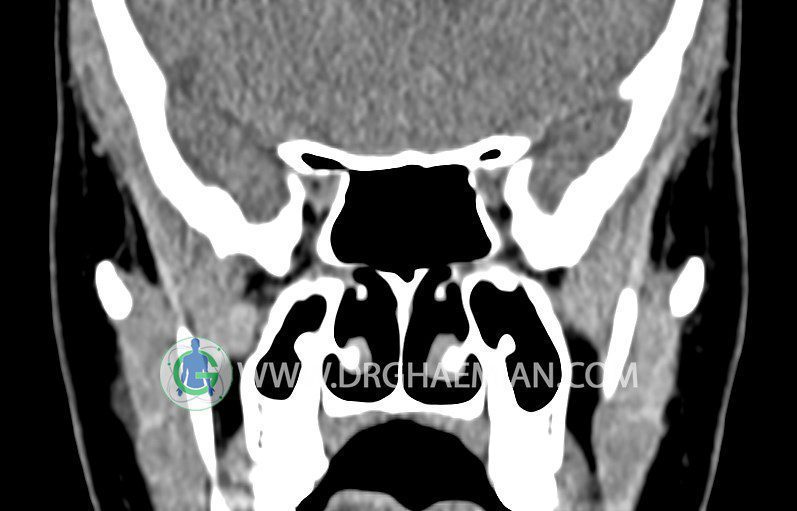

سی تی اسکن سینوس ها یک روش تصویربرداری است که با استفاده از تشعات ایکس تصاویری با جزییات از ناحیه خالی داخل صورت (سینوس ها) ایجاد میکند. در این کیس استئوم فرعی سینوس در دیواره سینوس ماگزیلاری، انحراف سپتوم و کونکا بولوزا مشاهده می شود.

در HRCT اسپيرال از سينوس هاي پارانازال مقاطع کرونال و آگزيال ( 16 اسلايس و مقاطع ظريف 1.5 mm بدون فاصله ، با پنجره استخواني و نسج نرم ) :

– انحراف سپتوم مياني بينی به راست

– کونکا بولوزا در کونکای ميانی چپ و

– اوستيوم فرعي در ديواره مديال سينوس ماگزيلاري راست

مشهود است .